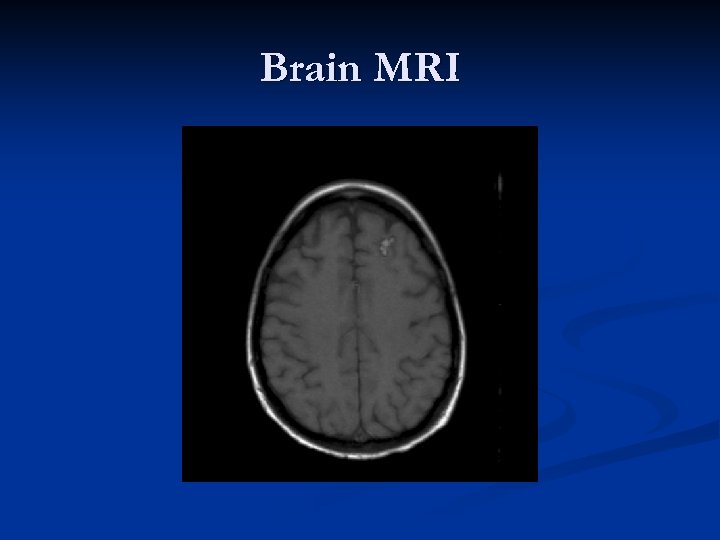

Head CT

Head CT n n FINDINGS: Intraparenchymal hemorrhage in the right parietal lobe has intervally increased in size, measuring approximately 5 cm x 3. 3 cm with extensive surrounding vasogenic edema. Interval development of a new, smaller foci of intraparenchymal hemorrhage within the bilateral frontal lobes and right temporal lobe, as well. Mass effect upon the left ventricle, with near effacement of the temporal and occipital horns. There is slight rightward midline shift.